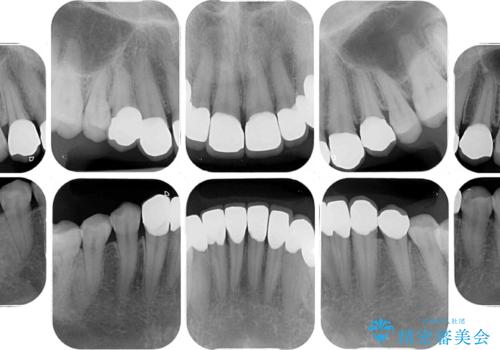

- 上下前歯や奥歯の虫歯治療を希望して来院された患者様です。

全顎的にむし歯が多く、根管治療の必要奥歯や、審美的に気になっている前歯を中心にオールセラミッククラウンにて補綴治療を行うこととしました。